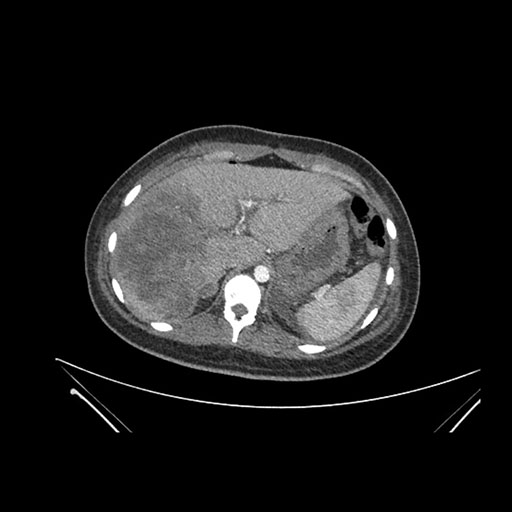

Imaging Analysis

Look through the patient's CT scan to identify any areas of concern for the necessary procedure.

Axial Venous

Based on initial findings, which issue(s) would you be most concerned about?